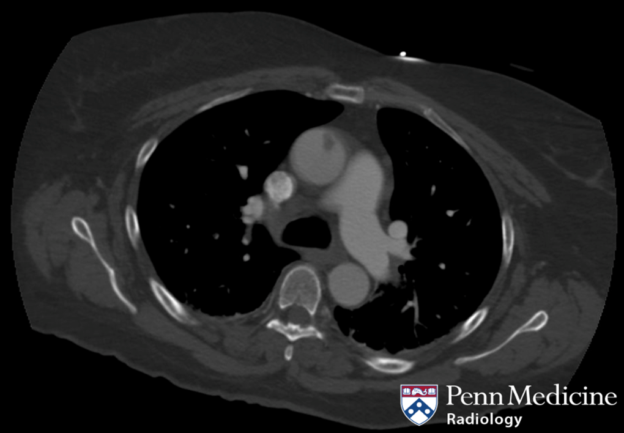

A 48-year-old woman presented with a cold left lower extremity requiring a left lower extremity embolectomy.